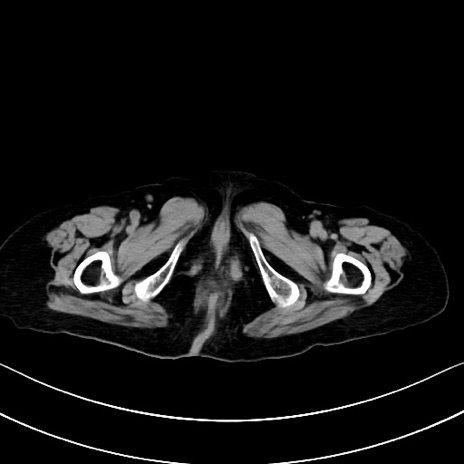

横断像

他院CT